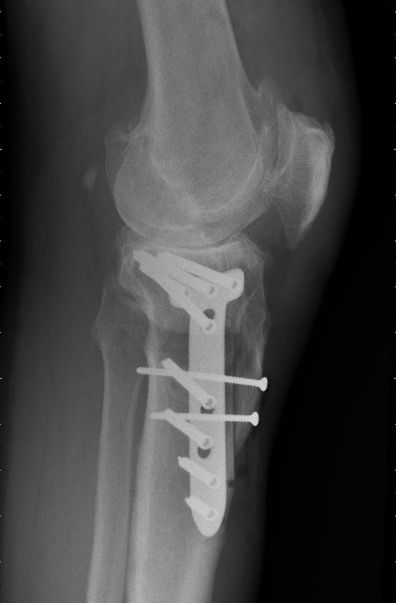

Although the medial open wedge and the lateral closing wedge tibial plateau osteotomies have comparable results in long term courses with correct postoperative alignment [11], the risk of injury to the peroneal nerve is lower in medial open-wedge tibial valgus osteotomy; moreover, it requires no fibula osteotomy and the fine adjustment of the correction angle is simpler [9]. We now perform a lateral closing wedge tibia osteotomy only in cases of a pre-existing leg length difference or a patella baja. However, biplanar descending osteotomy is an alternative in patella baja. There the osteotomy of the tuberosity is tapered towards the distal side and should be fixed with 2 screws (Fig. 9a).